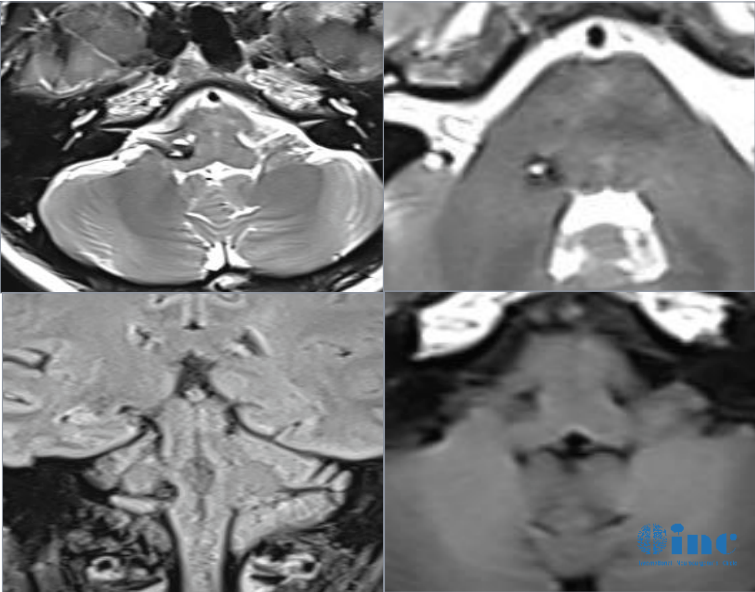

比如近期远程咨询中,31岁的脑干海绵状血管瘤患者陈先生,因出现身体、脸部麻木,还有听力下降、头晕等症状,就诊后怀疑是脑干海绵状血管瘤引起的出血,10多天病情恶化、无法独自行走。

关于目前是否需要尽快手术,巴教授这样评估:

“在核磁共振成像上看到的是新出血。如果我们看T2序列的图像,我们还可以看到周围水肿,这表明出血是新鲜的,对于手术来说,这实际上是较佳时机。如果再等一两个月,血液会被部分吸收,但疤痕的形成会增加手术的难度。因此,现在是手术的好时机”